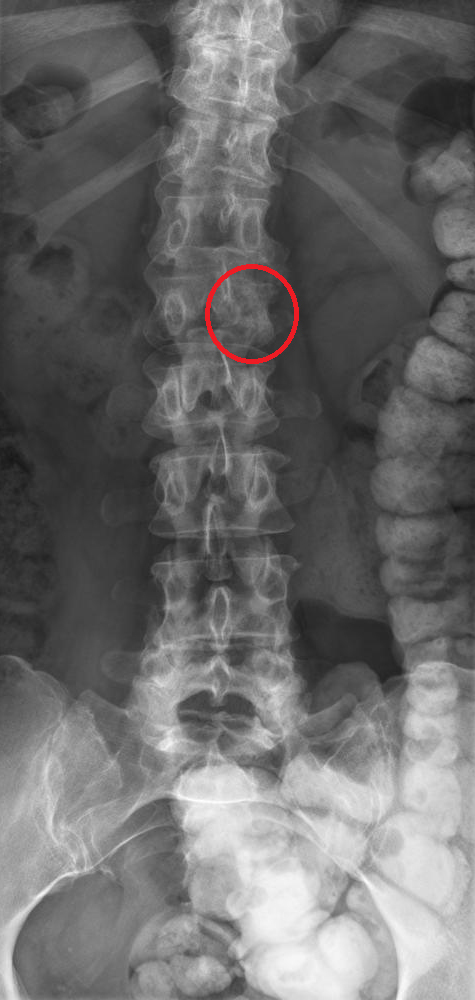

La mammographie montre l’aspect suivant :

Question 4 - Vous tirez les conclusions suivantes :

Il s’agit du quadrant supéro-interne, ce qui correspondait par ailleurs plus à la clinique.

On voit une anomalie (microcalcification) et la mammographie est donc à classer au moins ACR2. Par ailleurs, cette mammographie serait probablement classée ACR5.

Il faut réaliser une micro-biopsie (ou macro-biopsie si la lésion est difficilement palpable)

Pour rappel, concernant la classification de l’American College of Radiology (ACR) sur l’aspect d’une mammographie :

– ACR1 : mammographie normale ; – ACR2 : anomalie bénigne (pas de surveillance ni d’examen complémentaire) ; – ACR3 : anomalie probablement bénigne à surveiller : surveillance à court terme (mammographie à 3-6 mois) ou biopsie ; – ACR4 : anomalie suspecte nécessitant une histologie → microbiopsie ou macrobiopsie selon la situation ; – ACR5 : lésion d’allure maligne → microbiopsie ou macrobiopsie.

Par ailleurs, pour la lecture d’une mammographie, il faut retenir les repères suivants :

– sur le cliché de face : quel que soit le sein, la partie supérieure du sein représente le quadrant externe, et la partie inférieure représente le quadrant interne ; – sur le cliché oblique externe : au-dessus du mamelon = quadrants supérieurs, en-dessous = quadrants inférieurs.

Ci-joint un cliché pour vous aider à comprendre cette mammographie :